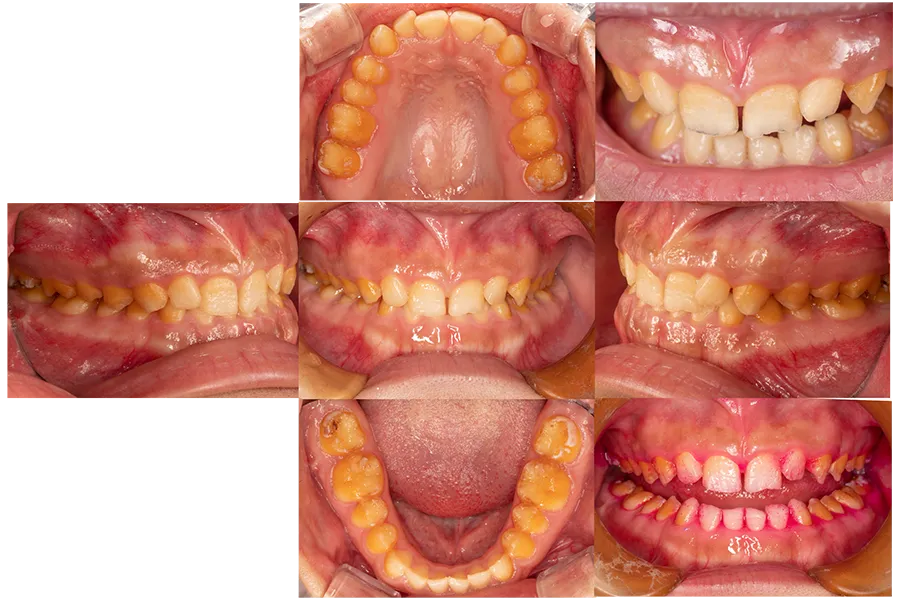

遺伝性エナメル質形成不全による

咀嚼障害に対する

全顎セラミック治療の症例

大学病院小児歯科専門医より、遺伝性エナメル質形成不全による咀嚼障害の患者様をご紹介いただきました。

診査・診断

遺伝性エナメル質形成不全は、歯の表面のエナメル質が正常に形成されない先天的な疾患で、

- 歯が欠けやすい

- 咬み合わせが崩れる

- 咀嚼しにくい

- 歯の見た目にコンプレックスがある

といった症状が生じることがあります。

本症例では歯の摩耗や破折が進行し、咀嚼機能の低下と咬合の崩壊が認められました。

治療前の状態

エナメル質形成不全により歯質が弱く、

歯の咬耗や破折が認められました。

また、咬み合わせの高さ(咬合高径)の低下も認められ、十分な咀嚼が困難な状態でした。